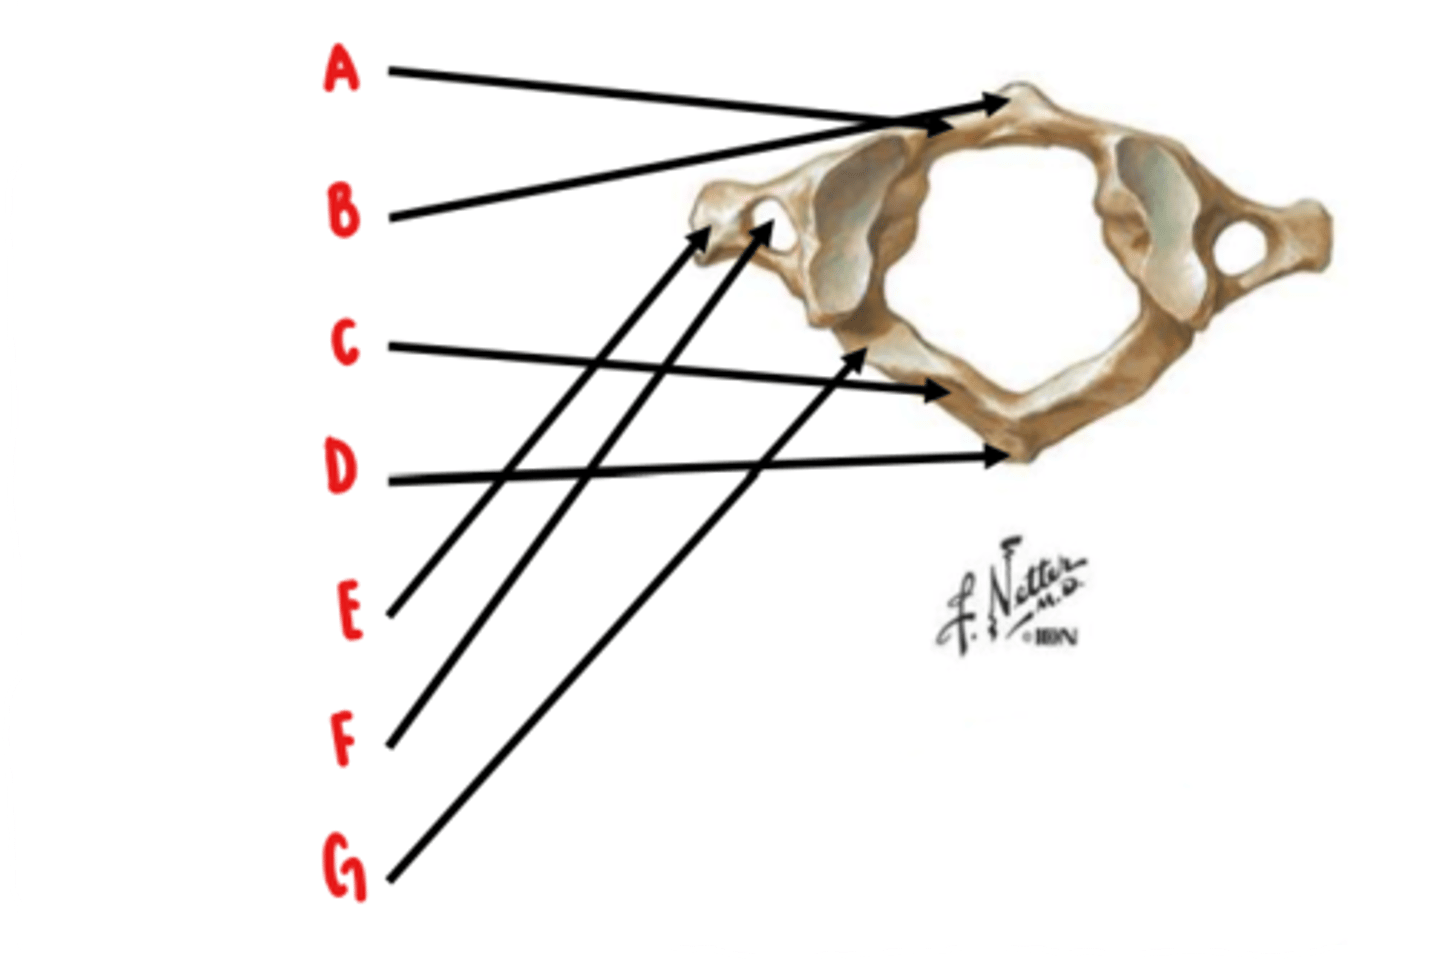

Atlas (C1)

What vertebrae is this?

anterior arch

Identify A

anterior tubercle

Identify B

posterior arch

Identify C

posterior tubercle

Identify D

transverse process

Identify E

transverse foramen

Identify F

groove for vertebral artery

Identify G